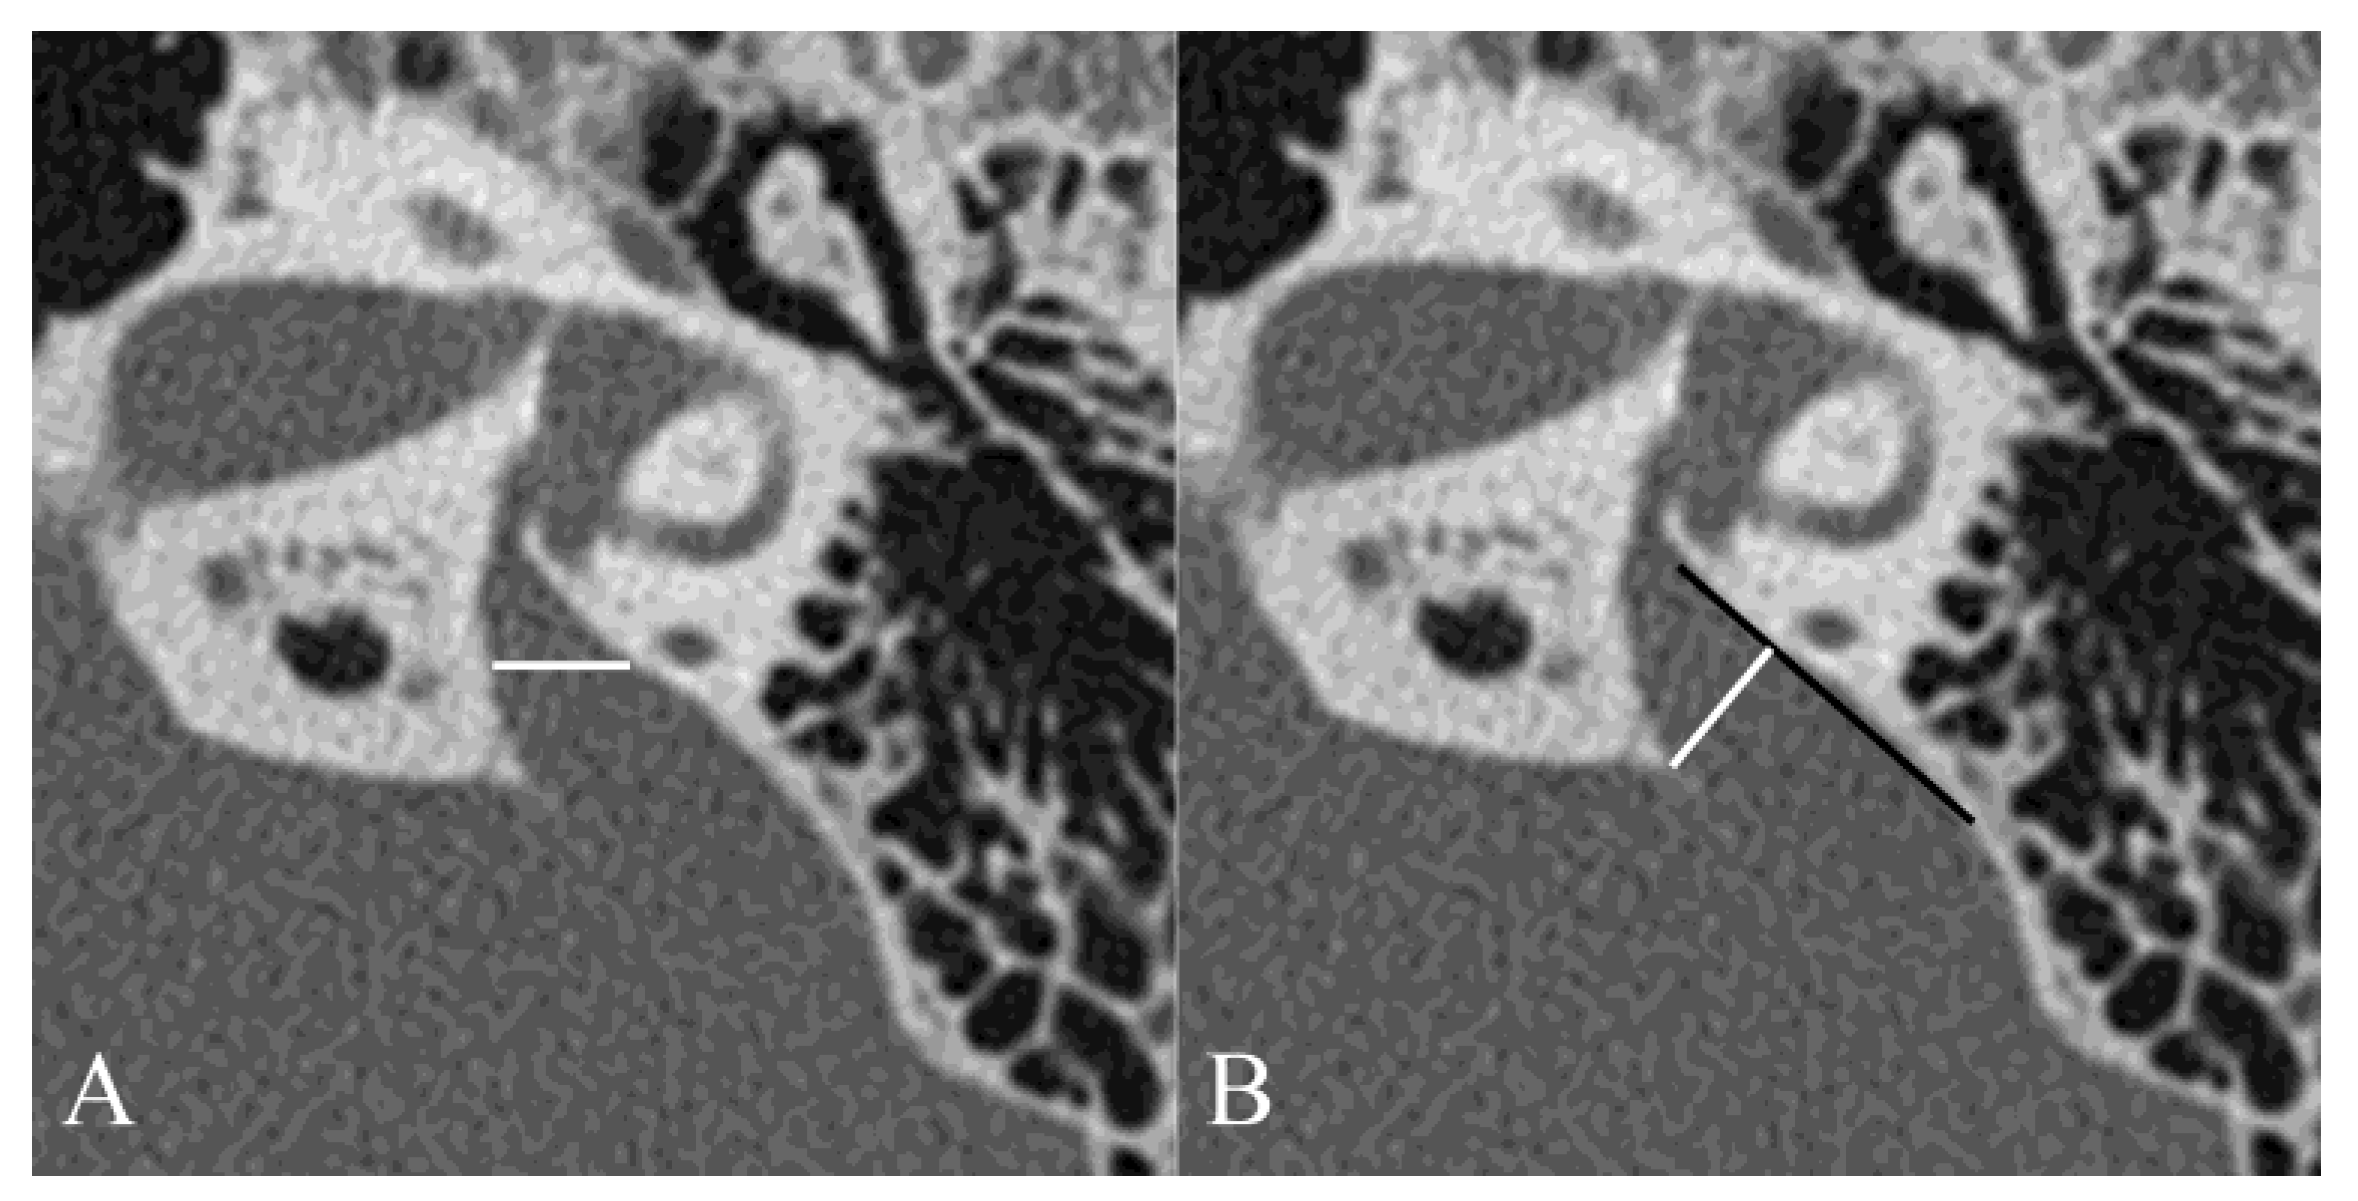

The VA width was measured using two different methods (Figure 1) [19]. The VA midpoint width was defined as the part of VA in the petrous bone located half the distance from its origin in the labyrinth to its aperture in the epidural space (Figure 1A). The VA opercular width was measured in the same plane as the endolymph sac depths by drawing a line from the opercular edge anterolaterally to form a 90° angle with the posterior wall of the petrous bone (Figure 1B) [19,20]. VA was measured by two neuro-otologists (GA and NN). Interobserver variability at the two measurement points was investigated.

Figure 1.

Measuring the VA midpoint and porous width in axial computed tomography images. The VA midpoint width (white line) was measured at the half the distance from VA fundus to its external pore (A). The VA porous width (white line) was measured from the opercular margins to the spots on the posterior temporal bone walls (black line) whose surface was perpendicular to the measurement lines (B).